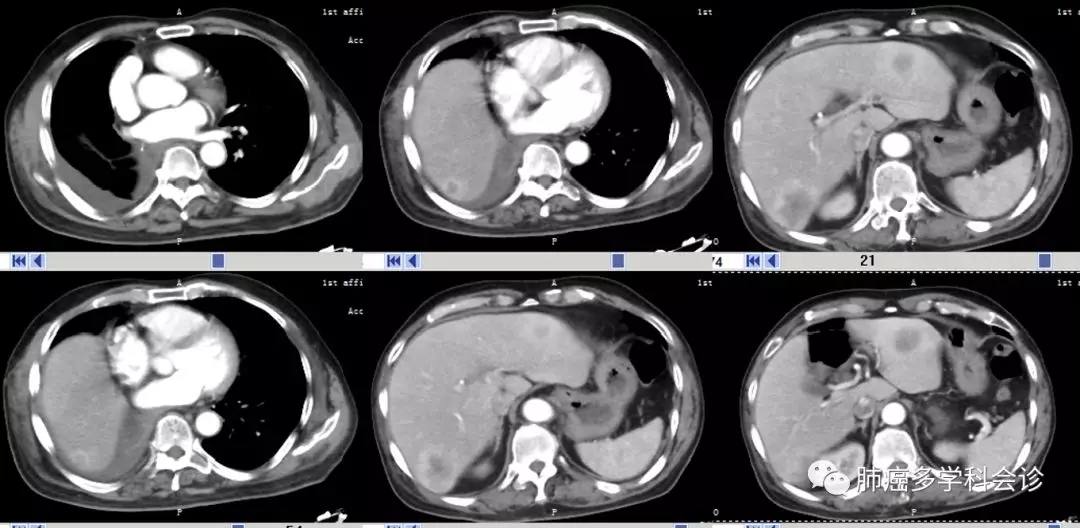

患者刘某某,男,65岁。2018-01因反复发热就诊,胸部CT(01-28):右肺门下占位,并右肺阻塞性肺炎、肺不张;纵隔及右肺门淋巴结肿大;双肺炎症;右侧胸膜局限性肥厚。

2018-12-04复查增强CT:发现肝转移新发病灶:

4.webp.jpg

术后复发分期:右肺腺癌胸膜转移(T4N1M1)IV期